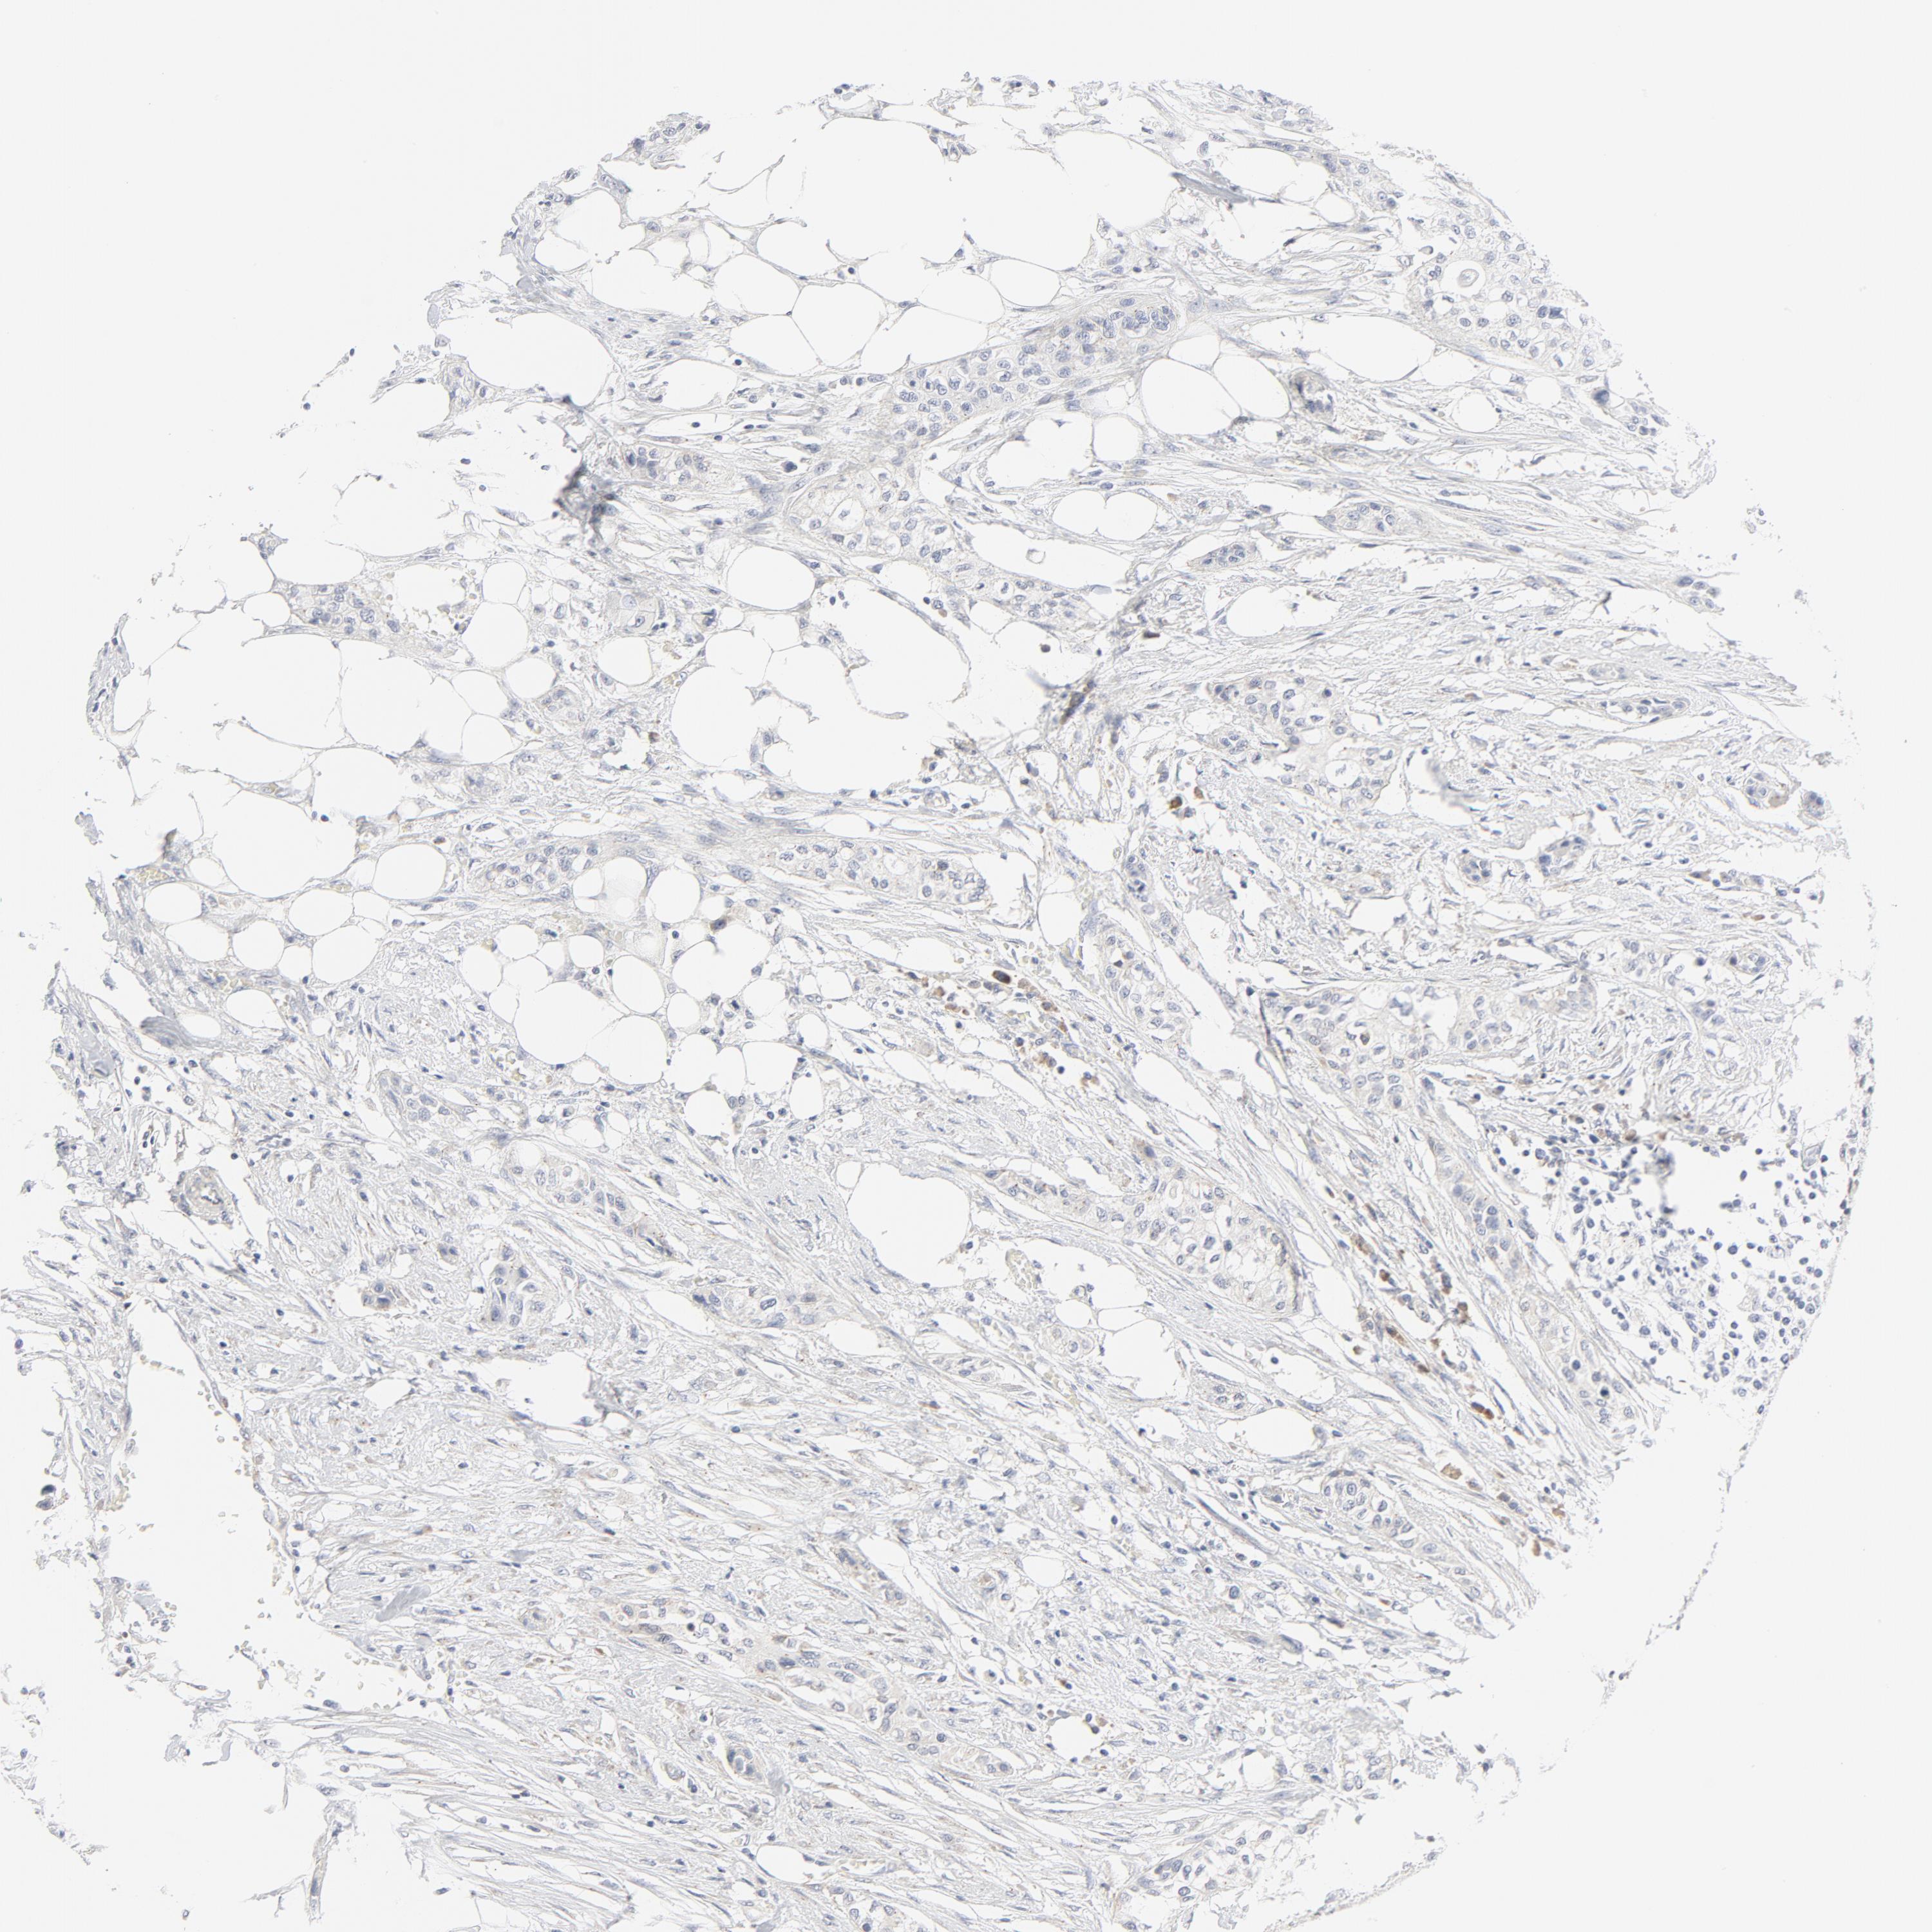

UROTHELIAL CANCER - Protein expressioni

A mouse-over function shows sample information and annotation data. Click on an image to view it in a full screen mode. Samples can be filtered based on level of antibody staining by selecting one or several of the following categories: high, medium, low and not detected. The assay and annotation is described here.

Antibody stainingi

Antibody staining in the annotated cell types in the current human tissue is reported as not detected, low, medium, or high, based on conventional immunohistochemistry profiling in selected tissues. This score is based on the combination of the staining intensity and fraction of stained cells.

Each image is clickable and will lead to virtual microscopy that enables deeper exploration of all samples and also displays staining intensity scores, fraction scores and subcellular localization as well as patient and tissue information for each sample.

Antibody HPA029925

Antibody CAB004490

Urothelial carcinoma, Low grade

Urothelial carcinoma, High grade